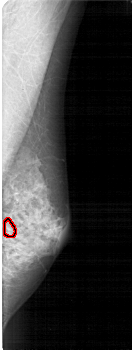

FILE: A_1867_1.RIGHT_MLO.OVERLAY

TOTAL_ABNORMALITIES 1

ABNORMALITY 1

LESION_TYPE CALCIFICATION TYPE PLEOMORPHIC DISTRIBUTION CLUSTERED

ASSESSMENT 4

SUBTLETY 2

PATHOLOGY BENIGN

TOTAL_OUTLINES 1

BOUNDARY

RIGHT_MLO LINES 5236 PIXELS_PER_LINE 1966 BITS_PER_PIXEL 12 RESOLUTION 43.5 OVERLAY